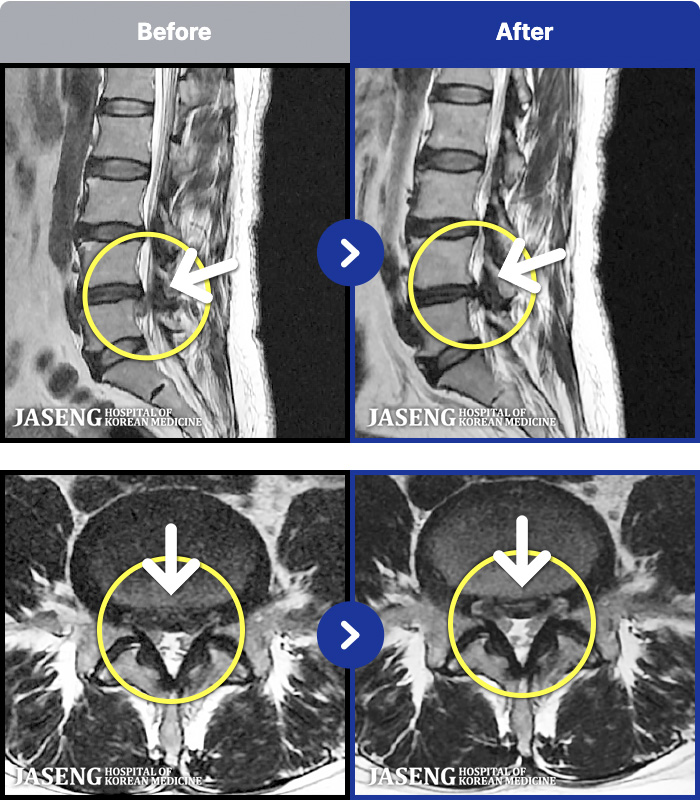

ȯںп Ǹ ǿ ԿǾ, ο ġ ۿ Ƿ ġḦ Ͻñ ٶϴ.